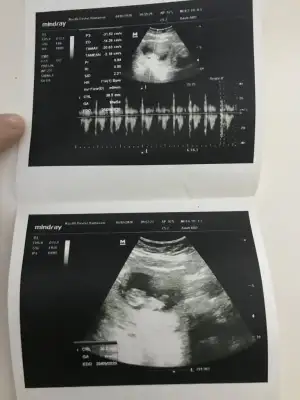

Kız gibi emin olmadım ögrenmedinizmi 24 hafta görünüyor takviminiz

Bencede kız gibi yaKız gibi emin olmadım ögrenmedinizmi 24 hafta görünüyor takviminiz![]()

Vallaha bencede tüm belirtiler de kız diyor çünkü ilk hamileliğimin tam tersiBunlara göre kız sanki nette değil usg ama kese kız yönündedetaylı taramamı neydi 20-24 hafta arası giriliyor orada netleşmiş olmalıydı